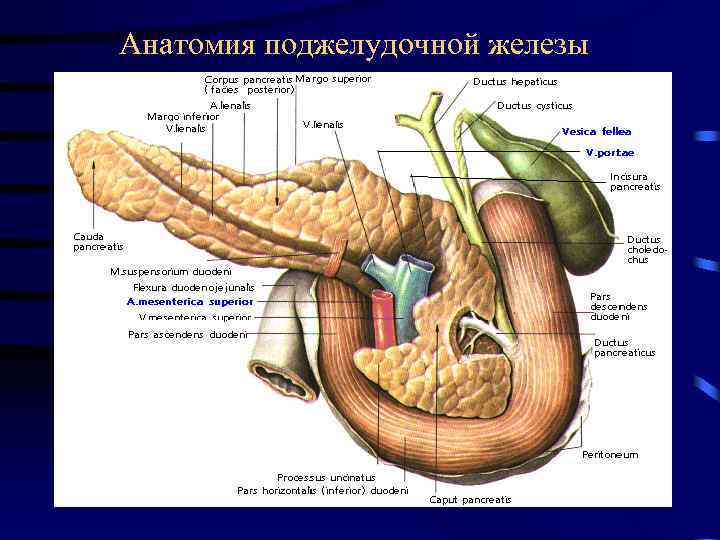

Анатомия поджелудочной железы (вид спереди)

Анатомия поджелудочной железы